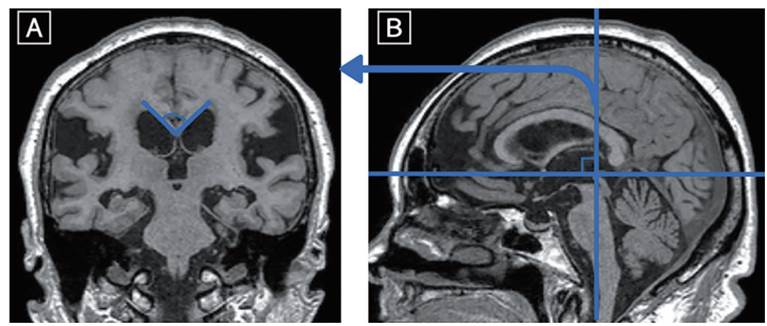

Angle of corpus callosum on coronal imaging

Cingulate sulcus

o Measured in sagittal plane - In NPH the posterior part is narrower